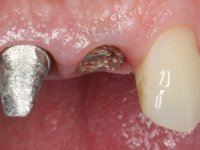

Endodontic treatments were performed and a metalic non screwed intra radicular post was placed on tooth 1.1. An alginate impression was made for laboratory confection of a reinforced acrylic provisional bridge, with teeth 1.1 and 2.2 as abutments and 2.2 as a pontic. After preparation of tooth 1.1 and root preparation of 2.1, the bridge was relined in mouth with self-polymerizable acrylic using a metal post for further retaining the prepared root canal on 2.1. Tooth 2.2 was cut at the gingival level to function as support. In the same session, the impression of the root canal of the 2.1 was made for the laboratory confection of a cast post and core. A double mixture technique with plastic tutor was used after previous canal vaseline with endodontic file and cotton. The provisional bridge was provisionally cemented and the cast post and core was made in the laboratory. Cast post and core cementation was made with resin-reinforced glass ionomer cement and the provisional bridge had to be readjusted to the new situation by removing the post at the site of 2.1. After careful surgical planning, a dental implant was placed, simultaneously with extraction of the root of tooth 2.2. The provisional bridge was placed by resting on the healing screw placed in the implant. The respected osteointegration period was 12 weeks, during which the provisional bridge was relined twice. After complete maturation of hard and soft tissues, definitive impressions were made. The gingival retraction technique was applied with an impregnated retraction cord and impression was performed using double mixture, open tray impression technique. A custom precious metal abutment implant was prepared in the lab, along with 3 metal caps to be used as infrastructures for the metal ceramic crowns. Particular care was taken in the confection of the cervical finishing line of the implant abutment, in order to follow the soft tissues emergence profile. Proof of infrastructures was done in the mouth being evaluated clinically and imagiologically. Collection of color information was done by the ceramist at the office. Ceramic was applied in the laboratory and the finished work was placed in the mouth after approval by the patient. Definitive cementation was made with resin-reinforced glass ionomer cement, and the first crown to be cemented was that of the implant, to facilitate removal of the excess.